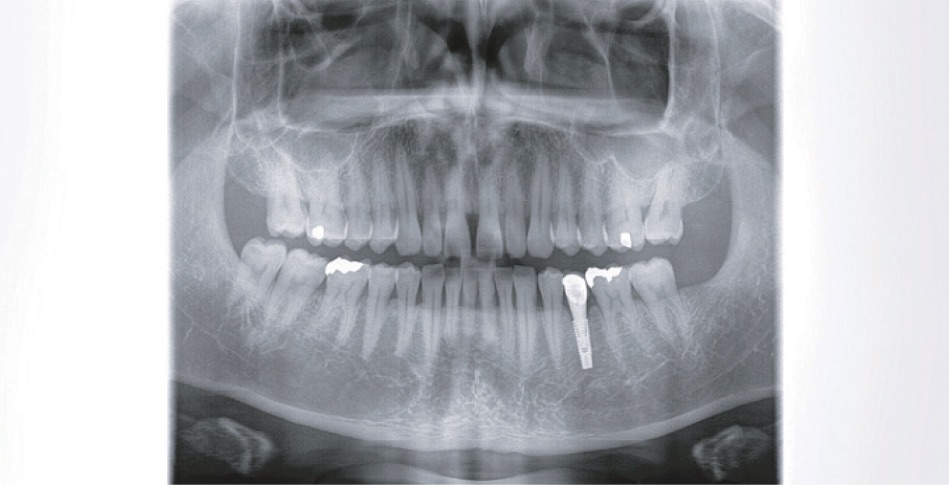

標準パノラマ撮影

分割パノラマ撮影